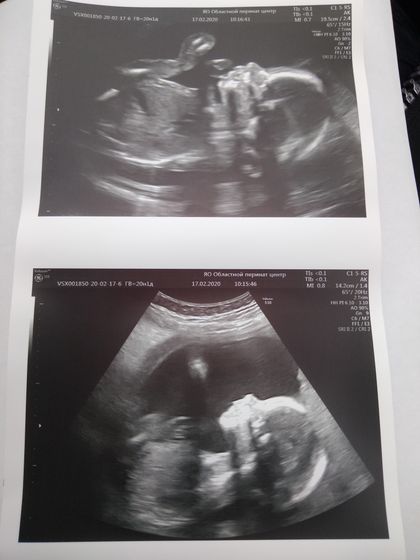

Все прошло хорошо. Мальчик у нас ? Растём хорошо. Вес 440гр. Все на месте, все развивается в норме. Увидела на УЗИ длинные ноги, засмеялась в голос. Ножки длинные, ровные, в мужа, он у меня высокий)) ? В, общем, теперь имя надо думать ? для девочек было много вариантов, а для мальчиков нетю ?

Здорово☺️ вот помню как вчера, тоже мальчика жду, в 20 недель были 258гр

Ростите здоровенькими) вы прям богатыри, у меня доча в 20 недель была 325 грамм или 375, уже не помню, ну и родились мы 3350 и 53 см.